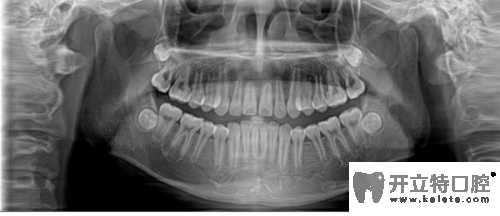

牙齒全景片

合肥崔勁松口腔正畸醫(yī)生說,矯正前做檢查是對顧客的牙齒和口腔健康負(fù)責(zé)。在做CT/全景片是能清楚的檢查到牙槽骨是否健康、有沒有牙周炎、阻生齒等情況,所以矯正治療前檢查是特別重要的。

其實,正畸前的全景片檢查也是為了能更好的了解口腔情況,例如牙齒囊腫、牙根被吸收、腫瘤等,如果正畸醫(yī)生不拍這個片子,在做矯正之前就不會發(fā)現(xiàn)這些情況,那就是屬于很不負(fù)責(zé)的做法。全景片還可以的測定牙齒傾斜角度、牙根情況、牙槽骨質(zhì)情況、牙周軟組織情況,解剖牙齒形態(tài)的測量,能讓醫(yī)生在矯正前依靠全景圖像更精準(zhǔn)的分析、設(shè)計治療方案。